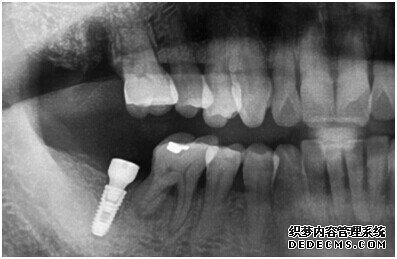

由CT片检查来看,刘女士口腔健康环境还是很好的,牙槽骨也适合种植牙的条件,而且由我们最后一颗牙是非常重要的,经过专家的建议和详细解释了原因之后,刘女士选择了美国百康种植牙。

种植牙整个过程完成后,刘女士非常满意自己的牙齿,并且表示以后一定会遵照医生的嘱咐好好注意自己的口腔健康,每晚一定会好好刷牙,饭后漱口,当然也会注意保护这颗种植牙!